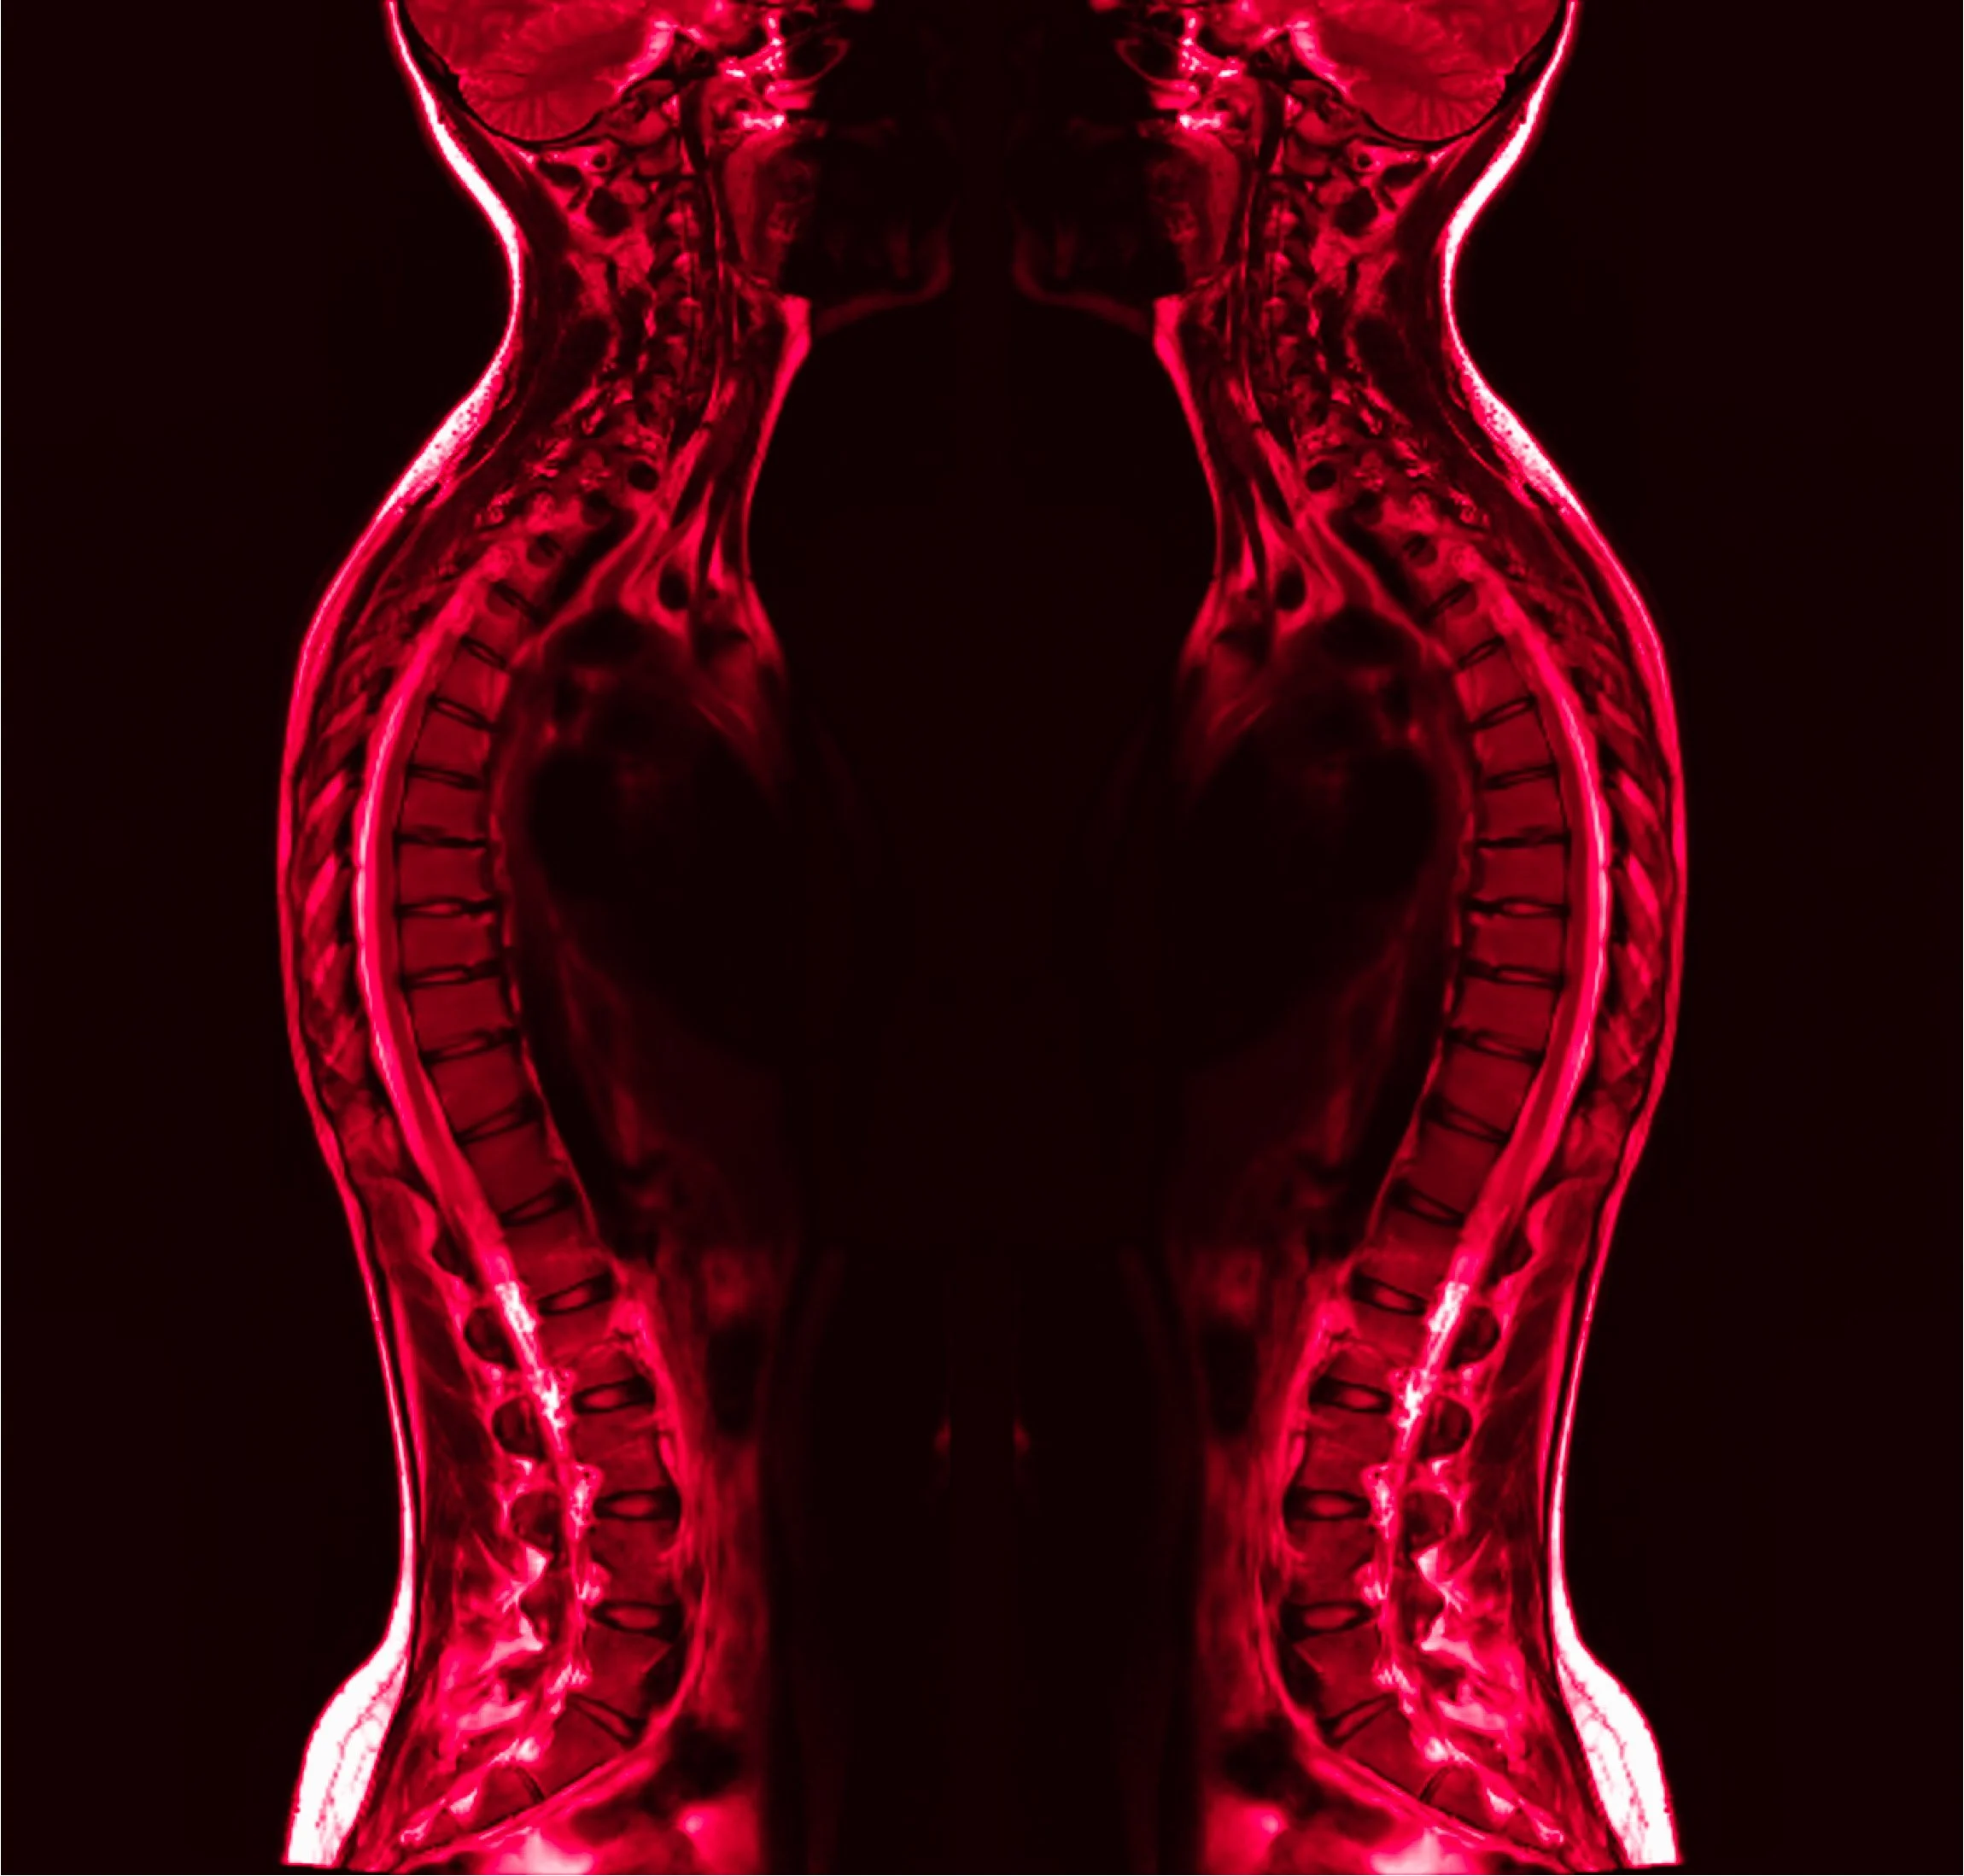

Confessions of a Bad-Backed Young Masc

Click each image to reveal its text.

Click each image to reveal its text.